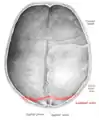

![]() Lambdoid suture (shown in red line) | |

The lambdoid suture (or lambdoidal suture) is a dense, fibrous connective tissue joint on the posterior aspect of the skull that connects the parietal bones with the occipital bone. It is continuous with the occipitomastoid suture.

The lambdoid suture is between the paired parietal bones and the occipital bone of the skull. It runs from the asterion on each side.

The lambdoid suture is named due to its uppercase lambda-like shape.